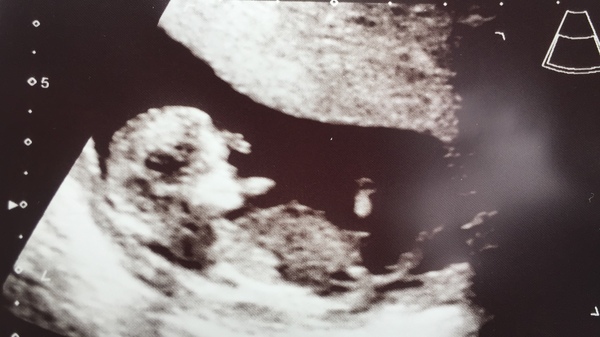

GoldilocksTheGraceless · 11/06/2018 20:32

Evening all :) had my scan this afternoon and luckily all was well!

Hope you can see little bean here on his/her tummy having a nice chill out!